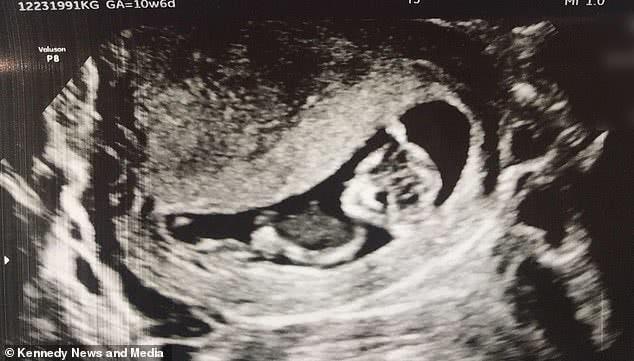

28歲的女子基斯萊沃尼亞·吉文斯在懷孕10周的時候她去做了超音波,發現是一對龍鳳胎,不過超音波顯示其中一個女胎兒較小,心跳聲也較弱,另一個男胎兒則看起來更健壯一些。

可到了第13周,當她再去做超音波時發現,較小的那個女胎兒已經神秘消失在腹中了。醫生們告訴吉文斯這是「雙胞胎消失綜合症」,也就是說雙胞胎之一死亡並且被母親或者是被另一個胎兒的身體吸收了。

為此,吉文斯特別傷心,為了紀念那個消失了的寶寶,甚至還為寶寶取了名字,並保留下了當時產檢時的超音波影像。